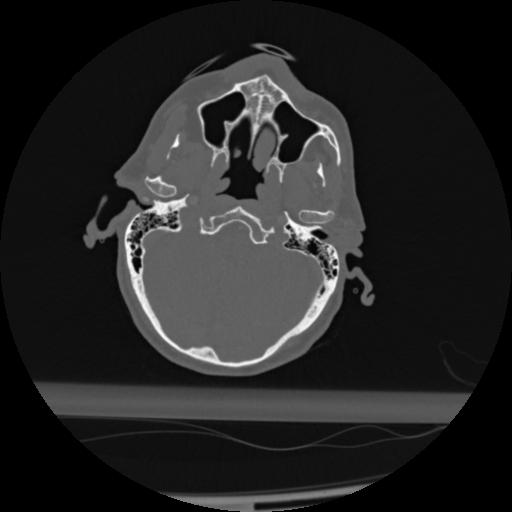

22 ANGIO,CE,Vol,0.5,ANGIO,,